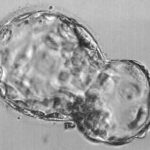

The two important cell types that are important for the development of a fetus are the inner cell mass and the trophectoderm cells. The blastocyst appears as a hollow ball with a clump of cells at one of its poles. This hollow ball is made of trophectoderm cells that later form parts of the placenta. These cells are necessary for implantation.

The clump of cells at one pole are called the inner cell mass. These are the cells that form the actual fetus. If an embryo contains only inner cell mass cells, the blastocyst cannot implant. If an embryo has only trophectoderm cells, the embryo can implant but a fetus is not formed and the result will be an early miscarriage.